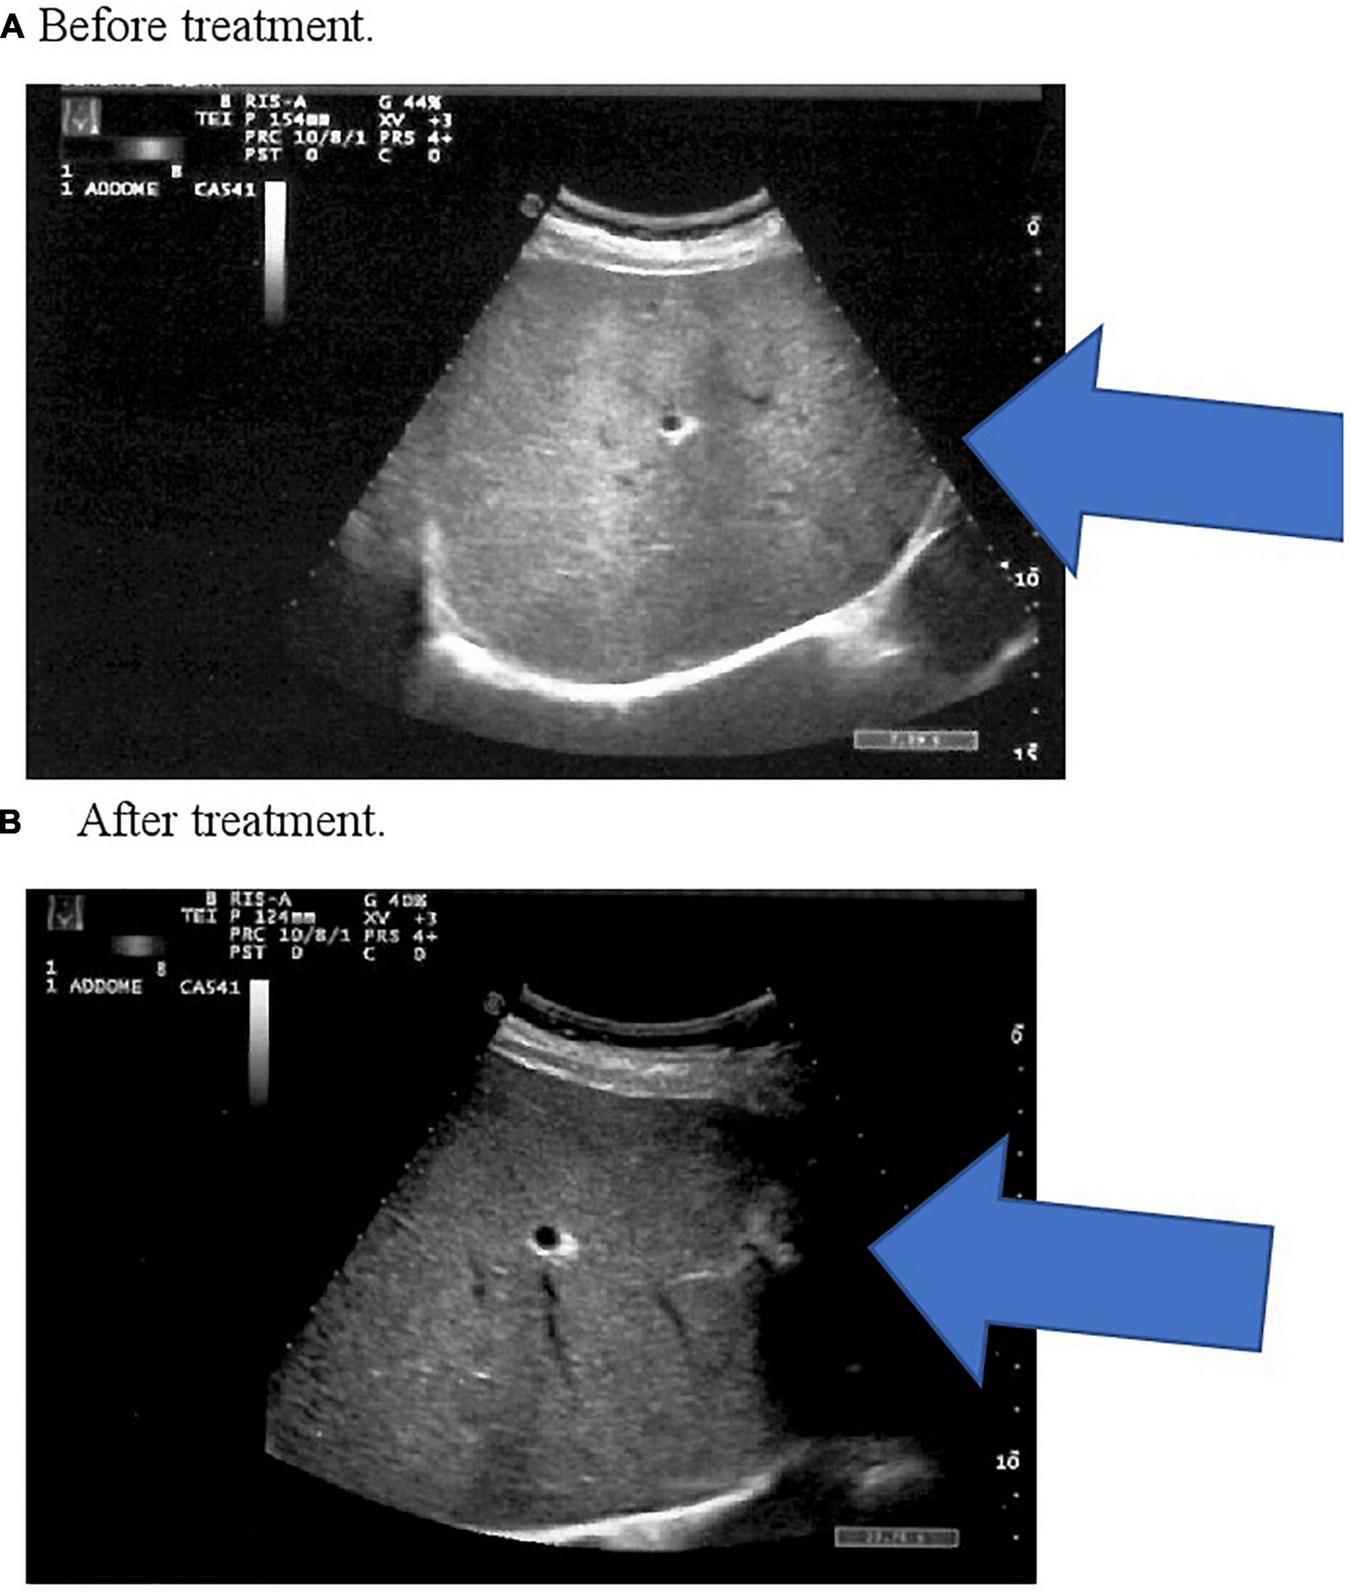

We observed a significant decrease in HSI after 3 months of VSL#3® treatment (p < 0.05 vs. baseline and p < 0.05 vs. placebo) compared with the placebo group (Table 2). All patients reported an improvement or the disappearance of hepatic steatosis (Table 3) demonstrated by the hepatic echography of patients subjected to control after 3 months of VSL#3® treatment (Figure 1).

Figure 1. (A) Before treatment. (B) After treatment. In panel (A) there is an increased echogenicity of the liver, a classic sonographic finding of hepatic steatosis. In panel (B) ultrasound image shows normal echogenicity of the liver parenchyma.